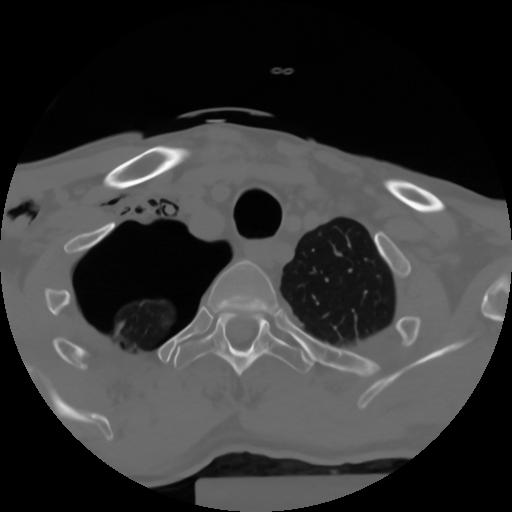

10 P.BLANDAS,,Axial,2.0,P.BLANDAS,,